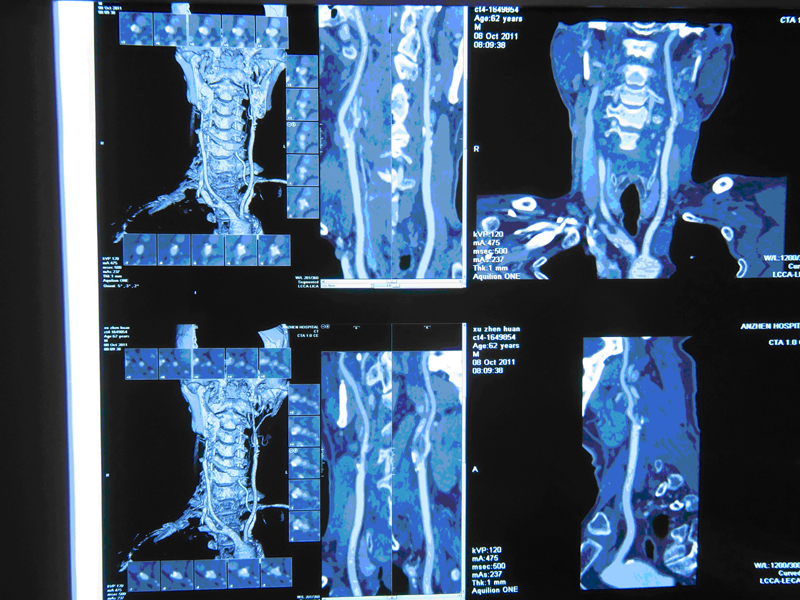

颈动脉CTA:头臂血管及双侧颈动脉呈动脉硬化性改变,右侧颈内动脉闭塞,左侧锁骨下动脉近段多发狭窄

头CTA+CTP:右侧颈内动脉颅内段闭塞,右侧大脑中动脉闭塞;右侧额叶脑梗塞;右侧大脑半球灌注异常

颈部血管超声:双侧颈动脉多发斑块形成,右侧颈外动脉起始处狭窄(>70%),右侧颈内动脉颅内段闭塞可能大,右锁骨下动脉斑块形成。

DSA检查:右侧颈内动脉闭塞,右侧颈外动脉狭窄,左侧颈内动脉狭窄。